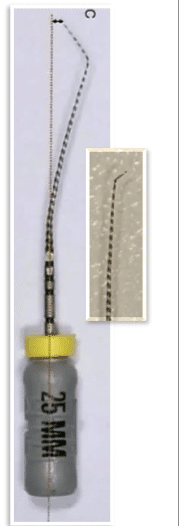

Step 3 — Pre-bend small file

Use #10 K-file with sharp bend at the last 2–3 mm.

A straight file will not find the pathway.